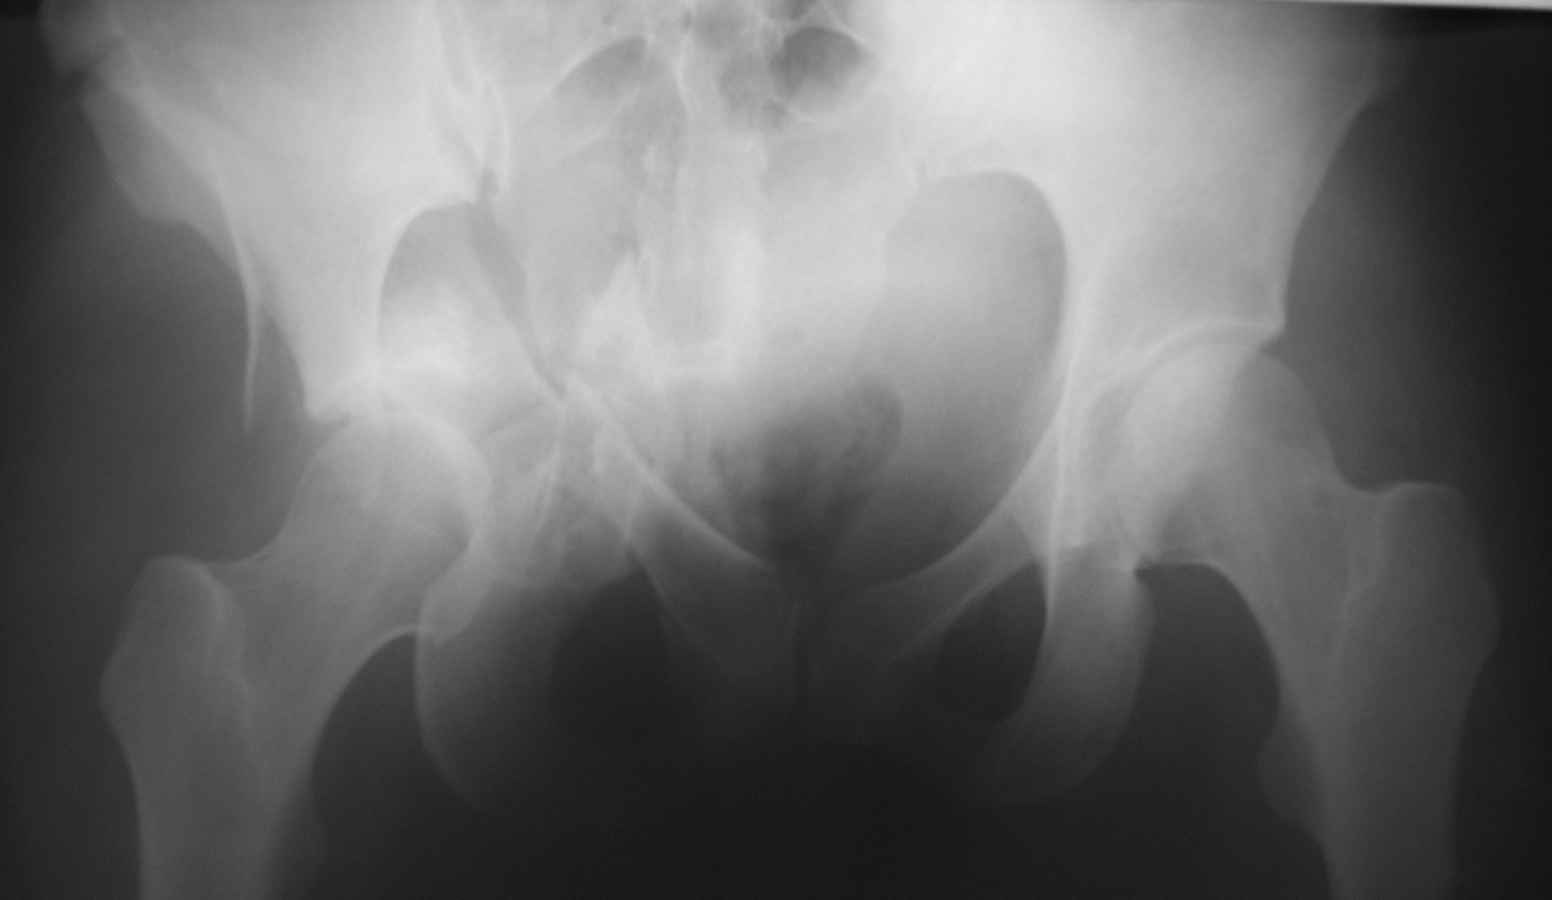

Уважаемые коллеги! Прошу вашего совета. Пациентке 28 лет. Травма в ДТП 13.11.10 - сбита

автомобилем. Первоначально было скелетное вытяжение, противошоковая терапия. Устранить

центральный вывих в палате не удалось. 23.11 под наркозом на ортопедическом столе закрытое

устранение центрального вывиха, снова наложено вытяжение. Сейчас - перед выбором, либо

идти на открытое вмешательство и восстанавливать переднюю колонну, либо продолжить

вытяжение до консолидации переломов с последующей костной пластикой и

эндопротезированием.